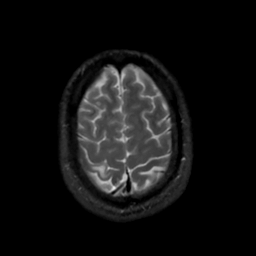

MR Study #7, March 24, 1991 -- Slice #42